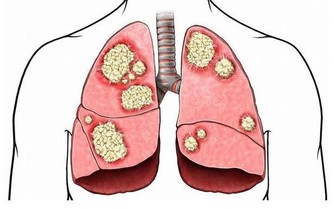

使我們的心臟得到很好的休息,恢復體力,並能起到殺死癌細胞的作用。